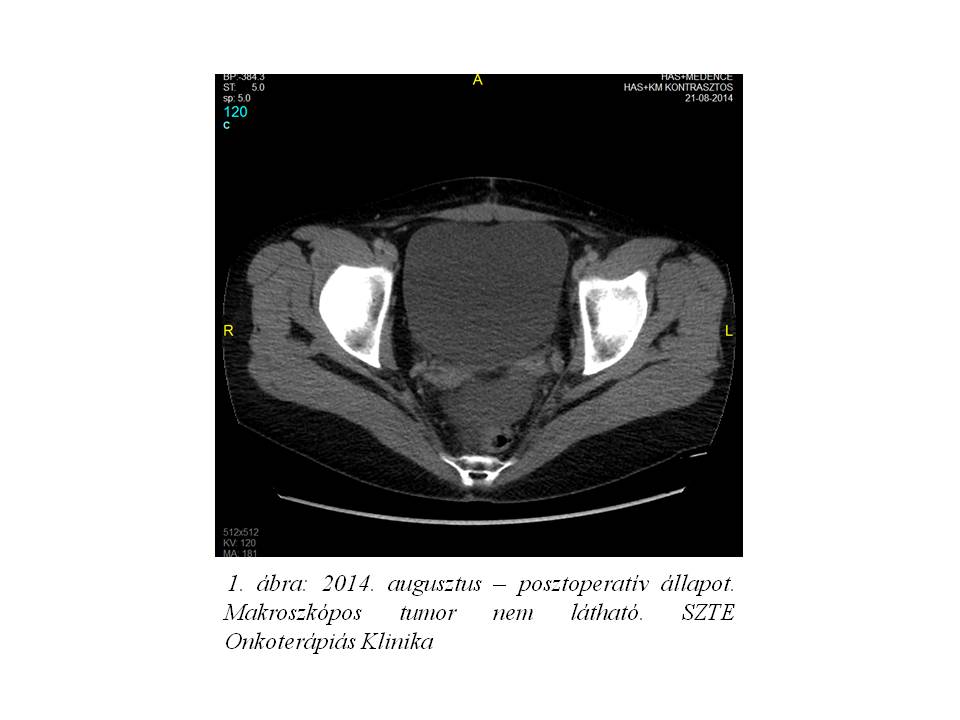

A posztoperatív has+medence CT vizsgálat eredménye makroszkópos tumor, távoli disszemináció, kóros lymphadenomegalia jelenlétét nem igazolta (1. ábra). Kontroll CEA: normál, CA-125: 182,3 U/ml értéket mutatott.